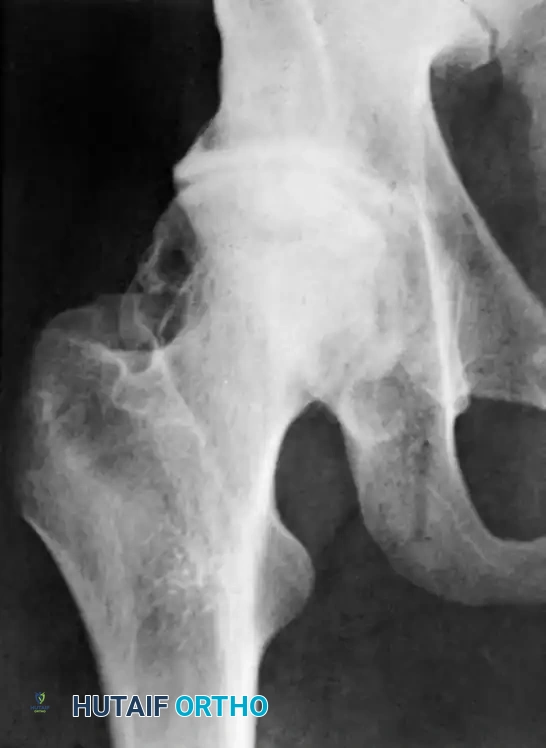

Osteomyelitis

When infection is confined strictly to the joint space, prompt arthrotomy and targeted intravenous antibiotic therapy usually prevent secondary osteomyelitis of the proximal femur.

However, if osteomyelitis does occur and results in sequestration of the femoral head in children under 12 years of age, the entire cartilaginous head may be totally reabsorbed. Alternatively, if the retinacular circulation is restored, the head may act as a scaffold and be replaced by new bone via creeping substitution.

In older children and adults, a devascularized femoral head typically remains as an infected, necrotic sequestrum that acts as a nidus for chronic infection. This requires formal surgical excision. While any approach can be used, the anterior approach provides superior exposure for complete head and neck resection.

In children, osteomyelitis of the ilium may also complicate septic arthritis (either as the primary source or a secondary extension). Both the joint and the ilium require meticulous drainage. In adults, impaired circulation may lead to pathological fractures of the femoral neck alongside sequestration.